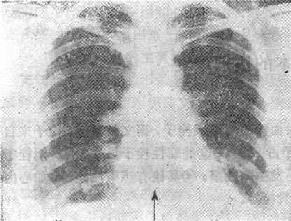

图5-2 犬模型

犬结扎左前降支冠状动脉后3-7天,程序刺激室间隔,当s1s2配对间期缩短到260~180ms,诱发室速(C、D、E、F)。发生时在缺血区(IZeg)记到低振幅舒张期碎裂电位。(选自El-sherif N 等:Circulation 1979;60,605-615)

应用信号放大及叠加的技术,提高信噪比可将适当滤波范围内的碎裂电位从体表导联上记到,这项无创性检查有利于在临床广为应用。目前做为商品的晚电位测定仪有两种,都是用微电脑自动检查、叠加和计算。经过动物实验,同步记录心内膜或心外膜碎裂电位和体表晚电位进行对照,获得几个参数:①标准QRS时间(ms);②总QRS时间(ms),即经过滤波的综合波群时限,自QRS起点至高频低幅超过噪声3倍处止;③QRS末、振幅低于40μV的时间(ms);④QRS波群综合向量均方根(μV);⑤QRS波群终末40ms以内综合向量的均方根(μV);以及叠加周期,噪音振幅等。Gomes等根据Simson设计的仪器,采用X-Y-Z导联测出的正常人总QRS时间<118ms,低于40μV的时间<38ms,终末40ms以内均方根>20μV。图5-3为正常及异常信号叠加心电图。

图5-3 正常与异常的信号叠加心电图

A.正常人;B.急性心肌梗死;C.陈旧性心肌梗死,曲线上涂黑部分为晚电位。